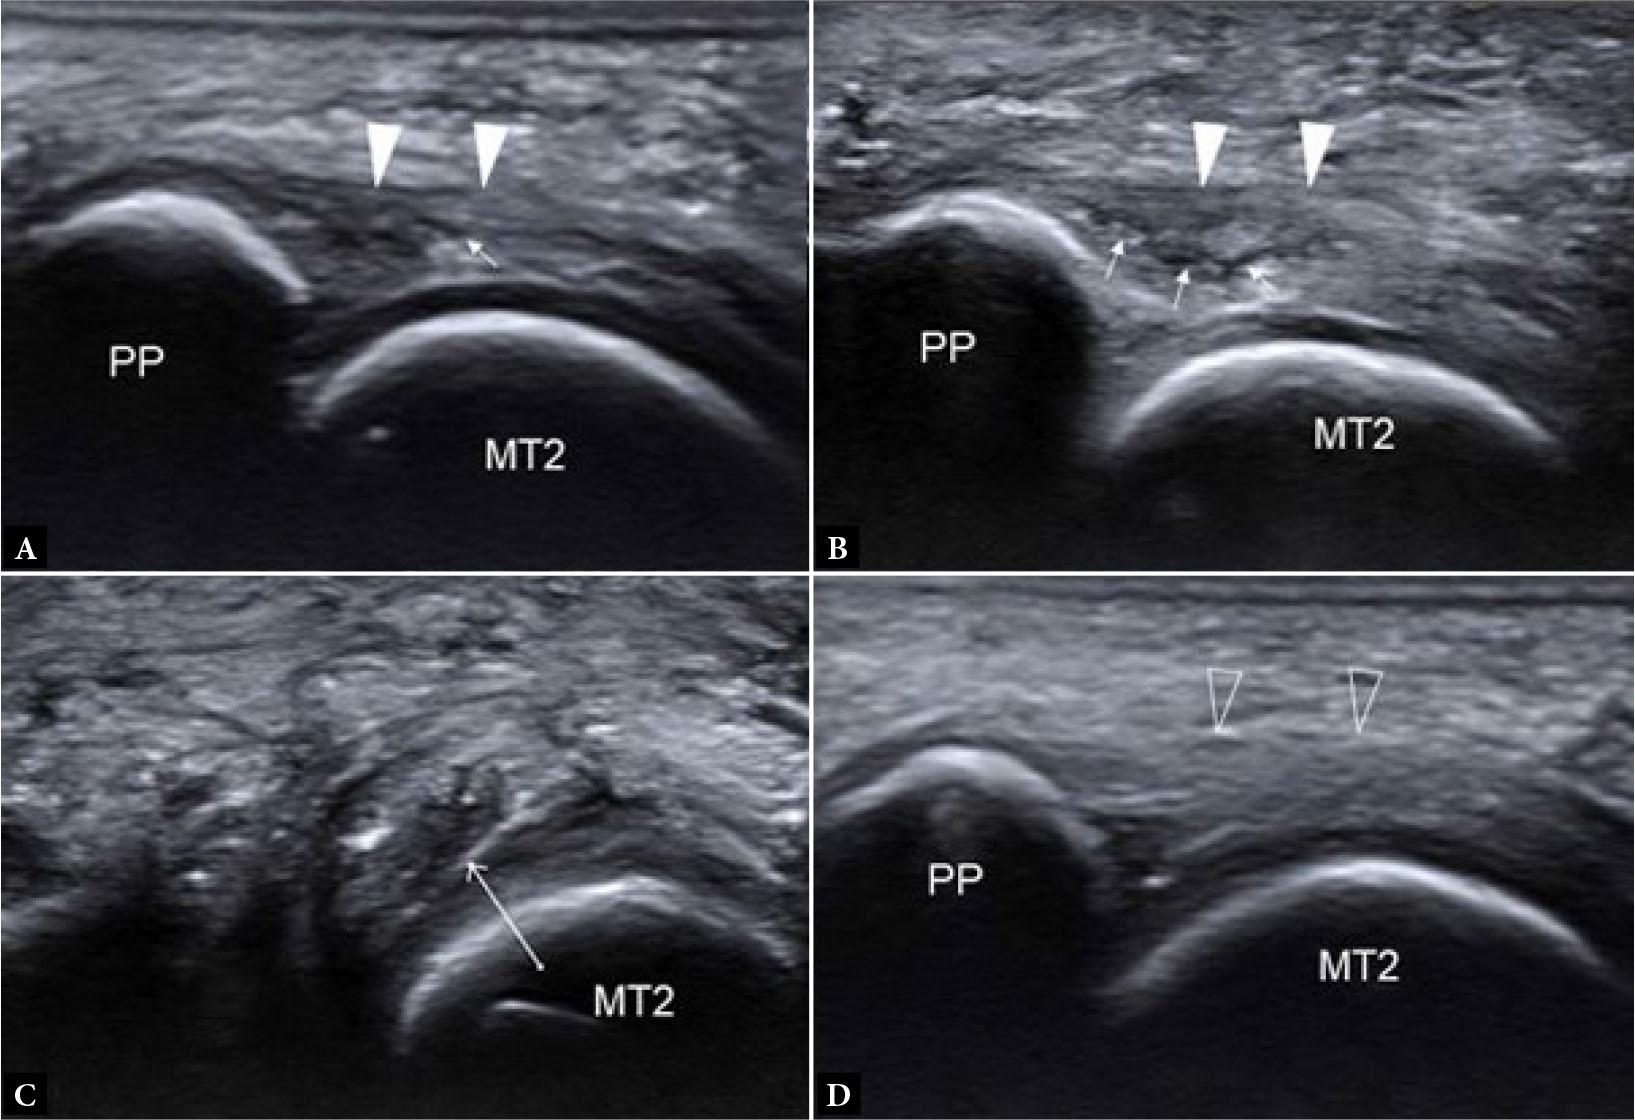

Lesser MTP joint plantar plate tear

Even more so than the 1st MTP joint, the plantar plates of the lesser MTP joints resist joint hyperextension and provide sagittal stability(11). Distally, the plantar plates are firmly attached to the proximal phalangeal bases while proximally, they are loosely attached to the metacarpal necks by fibro-synovial tissue(12). On either side, the plantar plates are firmly attached to the medial and lateral accessory collateral ligaments (Fig. 13) and, as such, co-existent injury of the plantar plate and accessory ligaments commonly occurs(12). Plantar plate tear can lead to MTP joint medial or lateral deviation, dorsal subluxation, and hammer toe(13). The normal plantar plate and plate tears are shown on US and MRI in Fig. 14 and Fig. 15. As with the 1st MTP joint, a midline hyperintense zone, measuring up to 2.5 mm long, at the phalangeal base is a normal anatomic recess(11) (Fig. 10). This is less frequently appreciated on US as a hyperechoic zone.

The 2nd, followed by the 3rd, MTP joint plantar plates are the most frequently injured(12). Plantar plate tears typically occur at the junction between the plantar plate and the accessory collateral ligament close to the phalangeal attachment, most commonly at the inferolateral aspect of the joint (Fig. 13). On US, most plantar plate tears are seen as discrete partial or full thickness hypoechoic defects in the plate substance(13,14). Flattening or attenuation may occur with plantar plate degeneration. When the plantar plate is completely torn, the flexor digitorum tendon may directly contact the metatarsal head(13,14). In the chronic setting, reactive pericapsular fibrosis can be seen as a non-compressible hypoechoic cuff of tissue abutting the plantar and inferolateral (or inferomedial) aspects of the MTP joint(13,14). US should be performed in both longitudinal and transverse planes, scanning the plantar aspect of the MTP joint slowly from lateral to medial and from distal to proximal, with angling of the transducer to avoid anisotropy. Most injuries occur at the distal attachment of the plate. Longitudinal US is best to detect and characterize tears while transverse US is useful to delineate the eccentric location of pericapsular fibrosis and to exclude subluxation of the flexor digitorum tendon. Longitudinal US during toe dorsiflexion can improve tear detection and appreciation of MTP joint subluxation(14).

For MR imaging, T1-weighted (T1W) coronal images are usually the most helpful as routine sagittal forefoot images do not always image the plantar plate in a true sagittal plane(12) (Fig. 15). Performing MRI in the prone position, with the foot in plantarflexion, results in less magic angle artifact and less movement artefact potentially facilitating assessment of the plantar plate(11). Prone positioning also leads to slight plantar shift of the interdigital soft tissues improving assessment of Morton’s neuroma(15). Dynamic US assessment during MTP joint dorsiflexion or during dorsal drawer (Lachman) testing can help assessment of plantar plate integrity and MTP joint stability. Compared with surgical findings, the pooled sensitivity (93%) of US for detecting plantar plate tears is comparable to that of MRI (89–95%), though MRI has a higher specificity (54–83%) than US (33–52%)(16). A negative US examination makes plantar plate injury very unlikely. If US is positive or equivocal, MRI can provide more specificity as to the nature of the injury and yield a more global assessment of the MTP joint(17).

Additional indirect MRI signs of plantar plate tear are joint effusion, subarticular BME, flexor tenosynovitis, an elongated 2nd metatarsal bone, and reparative pericapsular fibrosis while intermetatarsal bursitis and Morton’s neuroma are quite common accompaniments. Pericapsular fibrosis is a useful indirect sign of chronic plantar plate tear which often mimics Morton’s neuroma (i.e. ‘pseudoneuroma’)(11) (Fig. 16). Helpful features to distinguish between pericapsular fibrosis and Morton’s neuroma are listed in Tab. 3. It is likely that as pericapsular fibrosis/plantar plate tear becomes more widely recognized, less Morton’s neuromas and more chronic plantar plate tears will be diagnosed.